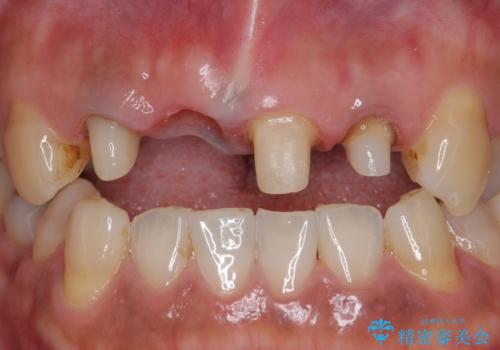

- 右上の前歯が折れてしまったので診て欲しいといらっしゃった方の症例です。

右上1番目の歯は保存不可能だったため抜歯し、ブリッジによる補綴を行いました。